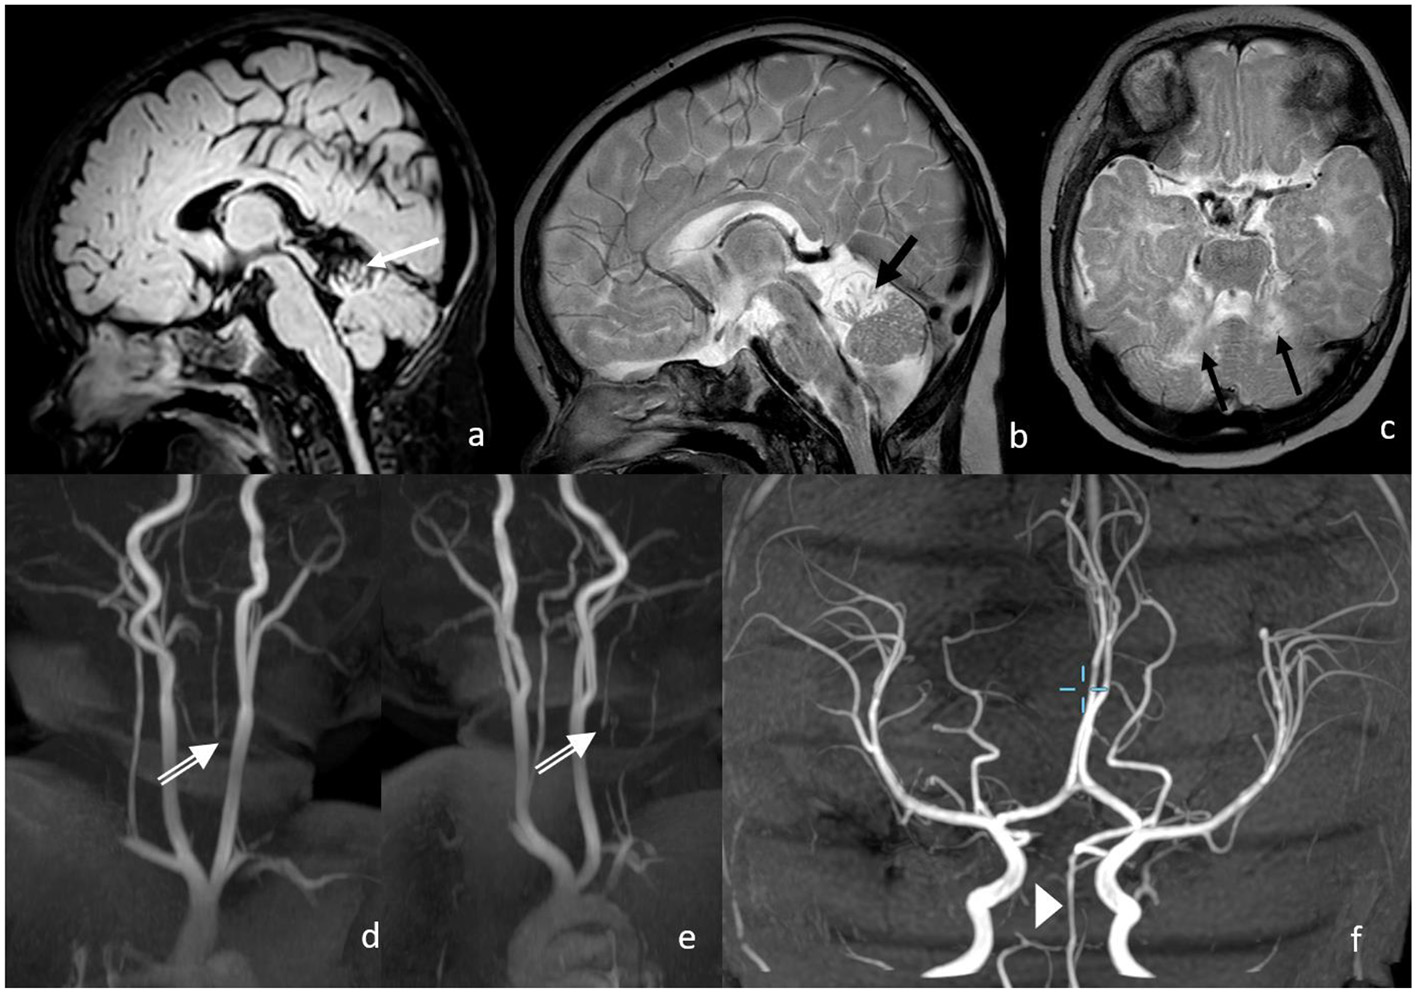

In the 3 months of the neurological follow-up examination, the evolution was appropriate to the age with a symmetrical activity of all the extremities. Intermittent strabismus, with abduction deficit of the right more than the left, was observed as well as a partially fixed head malposition with left rotation. The MRI showed a normal perfused basilar artery without signs of new ischemia (Figure 4). The cerebellum shows defects in the territory of the superior cerebellar artery with focal atrophy.

Figure 4

Three months following up of MRI and MRA. Postischemic defects in bilateral SCA territory with focal atrophy in the cerebellum on the following: (a) FLAIR (white arrow); (b,c) T2w (black arrows), proximal vertebral artery shows no antegrade flow in v0-V2 with distal reperfusion; (d,e) white double arrows; and (f) the basilar artery shows normal flow signal.